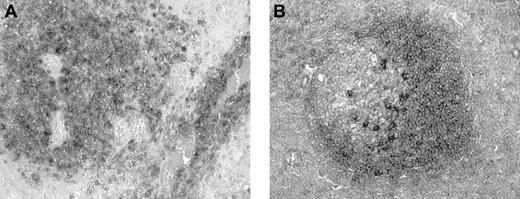

Brain biopsy specimens from 24 patients with non-Hodgkin B-cell PCNSL were studied. Specimens varied in size, most consisting of multiple pieces that varied from fragments measuring less than 0.1 × 0.1 cm to pieces measuring 2.0 × 0.9 cm. Microscopic examination revealed diffuse invasion of brain parenchyma by medium-sized or large atypical lymphocytes. The characteristic pattern of preferential concentric perivascular cuffing by malignant lymphocytes was observed in most cases, particularly in less densely infiltrated tissue or at the tumor periphery (Figure1). According to WHO criteria, 23 tumors were classified as diffuse large B-cell lymphomas and one tumor was classified as an atypical Burkitt lymphoma.

Histopathology of PCNSL.

Brain biopsy specimen from a patient with PCNSL shows infiltration of brain tissue by large malignant lymphocytes, with characteristic perivascular collections of tumor cells (hematoxylin and eosin, original magnification × 400).